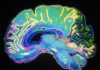

The analysis pointed to a number of changes in the mitochondria in the brain cells of mice exposed to frequent stress, compared to the non-stressed mice. Furthermore, testing of blood samples collected from patients with panic disorder after a panic attack also showed differences in mitochondrial pathways, suggesting that changes to cellular energy metabolism may be a common way that animals respond to stress.

The discovery that high levels of stress may substantially impact the functioning of the powerhouses of the cell opens up new avenues of research into stress-related diseases.